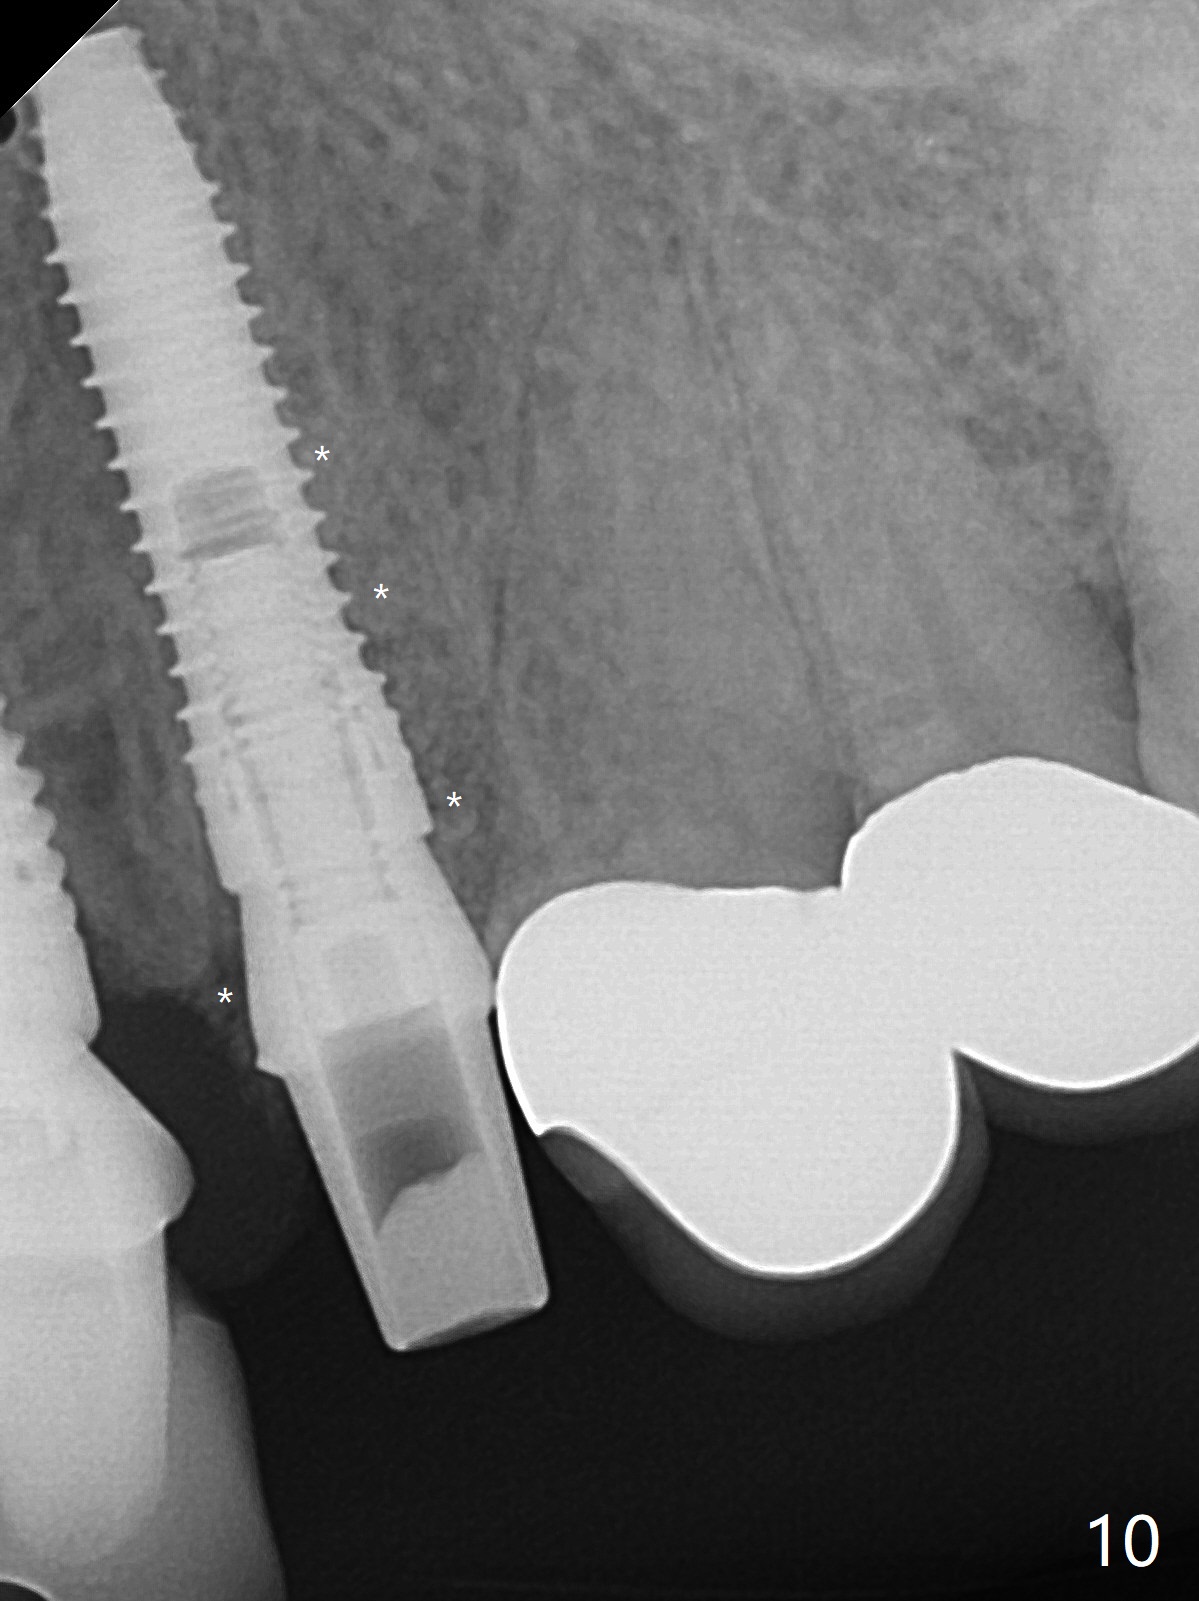

左上尖牙拔除前发现远中腭侧瘘道,拔除后发现相对牙槽嵴骨缺损(图一(术前CT):*),其实患牙根尖在颊侧骨板颊侧(图二:>),拔除后,根尖骨板缺损(图三:>),由于后者离颊侧牙槽嵴(图四:红箭头)远,骨粉修复重要性不如腭侧牙槽嵴(图四:白箭头),当窄植体植入后(图四:绿色),首先在腭侧植骨(图五:红圆圈),因为基台放置后(图六:粉红色),腭侧植骨开口狭窄(图六:白箭头)。即刻种植总是腭侧,颊侧间隙大,颊侧根尖缺损填骨应该容易(图七:橘黄色圆圈),即使不全(*),无关大局。徒手初步钻洞(图八),种植(图九)方向尚可,植骨好像完全(图十:*)。术后一周临时牙冠(11,尖牙)比侧切牙还短(图十一),随着愈合,尖牙牙冠会比双尖牙还短,因为植体偏腭侧,可能需要调整临时牙冠边缘。颊侧牙龈单纯疱疹感染,颊侧根尖仍有疼痛,腭侧瘘道缩小。